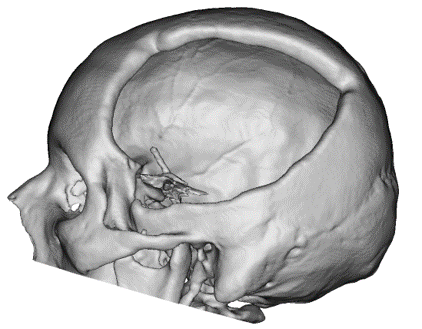

CASO CLÍNICO

Paciente masculino con un defecto de dimensiones aproximadas de 157.20×109.25mm el cual se reconstruyo con un implante en Peek.